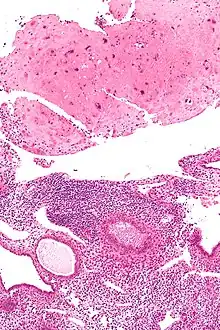

| Micrograph of a placental site nodule (top of image). H&E stain. |

Typically, they consist of pink (hyaline) material using the standard stain and contain few cells. Bizarre multinucleated cells may be present; however, there is no mitotic activity. The differential diagnosis includes (cervical) squamous cell carcinoma, gestational trophoblastic disease, and exaggerated placental site.